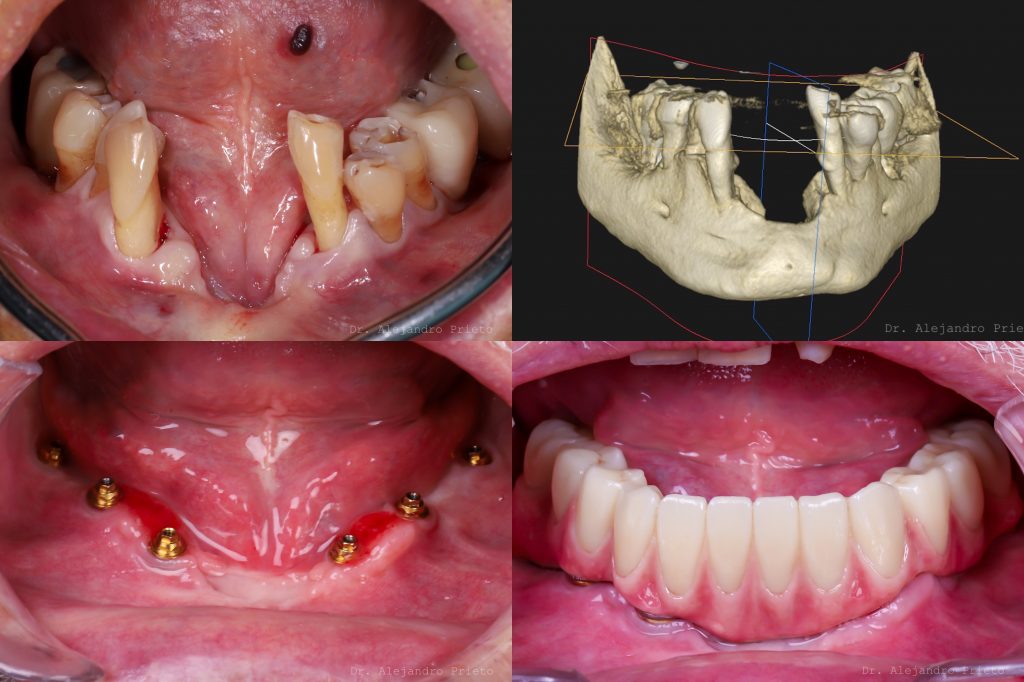

Un injerto de hueso dental es un procedimiento quirúrgico que estimula la regeneración de la masa ósea que da soporte al implante. Se hace por medio de materiales biológicos o sintéticos.

Un injerto de hueso dental es una técnica quirúrgica que permite aumentar la masa ósea en el maxilar o la mandíbula.

Mediante la implantación de material de injerto se promueve la regeneración de las células óseas con el fin de aumentar su volumen y restaurar tanto su capacidad de soporte como su estética.

Este tratamiento puede tener diferentes finalidades. La más habitual es proporcionar el soporte necesario para la colocación de implantes.

En Dr. Alejandro Prieto Dental somos especialistas en rehabilitaciones de boca completa con implantes

Historias de transformación

Si alguna vez te han dicho que tu caso no tiene solución, en Alejandro Prieto Dental desafiamos los límites de la odontología para ofrecerte la respuesta que estabas buscando.

Visualizar la transformación

Los cambios de imagen de la sonrisa favorecen mejoras cuidadosas y matizadas, para obtener resultados naturales que garanticen el equilibrio general y la armonía facial.